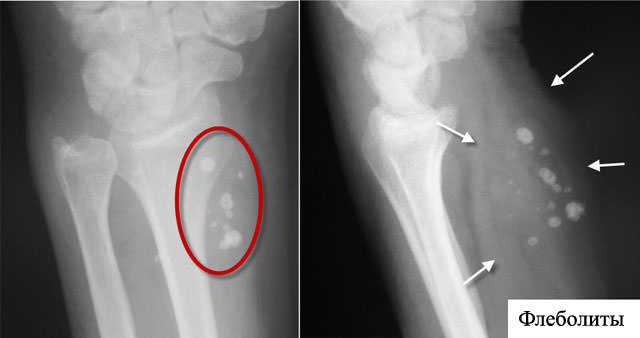

Рентгенограмма, как метод диагностики, подразумевает получение постоянного негативного изображения исследуемого объекта на пленке с помощью рентгеновского излучения. Часто этот способ называют просто «рентгеновский снимок».

При проведении рентгенограммы флеболиты вен обнаруживаются в качестве множественных теней. Чтобы отличить венозные камни от конкрементов (камней плотной структуры), специалисты исследуют не только структуру и форму образований, но и место их расположения.

Размер флеболитов обычно мелкий (в пределах 1–5 мм), чаще всего они округлой формы, плотные, как камень, прикрепленные к стенке вены. Редко можно встретить подобные образования размерами более 10 мм.

Наличие венного камня не нарушает движение крови, так как в большинстве случаев они не превышают 5 мм. В венозных сплетениях они могут быть множественными, напоминать виноградную гроздь, их количество иногда доходит до 100 и более штук. По структуре встречаются однородные образования и слоистые, когда чередуется отложение волокон соединительной ткани и кальция.

Проблемы возникают при обнаружении таких образований на рентгенограмме. Так как плотность, форма, размер, расположение флеболита и камней в мочевыводящей системе идентичны, то нужно знать отличительные признаки этих заболеваний: